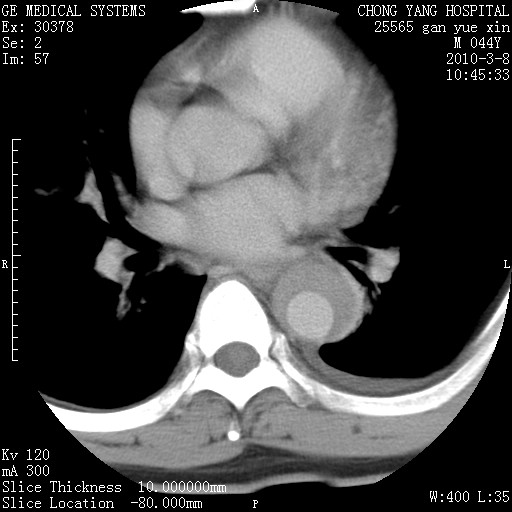

标题: CT24940:主动脉增强,典型病例。 [打印本页]

标题: CT24940:主动脉增强,典型病例。

夹层动脉瘤。

夹层动脉瘤,典型

主动脉夹层。

动脉夹层的分型:

⒈debakey分型:根据主动脉夹层累及部位,分为三型:ⅰ型:原发破口位于升主动脉或主动脉弓部,夹层累及升主动脉、主动脉弓部、胸主动脉、腹主动脉大部或全部,少数可累及髂动脉。ⅱ型:原发破口位于升主动脉,夹层累及升主动脉,少数可累及部分主动脉弓。ⅲ型:原发破口位于左锁骨下动脉开口远端,根据夹层累及范围又分为ⅲa,ⅲb。ⅲa型:夹层累及胸主动脉。ⅲb型:夹层累及升主动脉、腹主动脉大部或全部。少数可累及髂动脉。

⒉stanford分型:a型:夹层累及升主动脉,无论远端范围如何。b型:夹层累及左锁骨下动脉开口以远的降主动脉。

夹层动脉瘤,少量胸水

夹层动脉瘤;左侧少量胸腔积液。